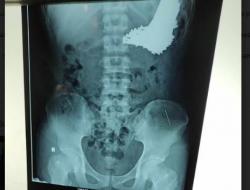

Setelah ditelusuri terdapat beberapa peningkatan ini terjadi di beberapa lokus. Yang pertama terdapat di lokus kelompok dokter bedah. Dimana salah satunya terlambat mengidentifikasi pasien Covid-19 yang sudah dilakukan operasi.

"Jadi ini salah satunya adalah terlambatnya identifikasi pasien Covid-19 itu sendiri sehingga diketahui setelah dilakukan operasi,” katanya.